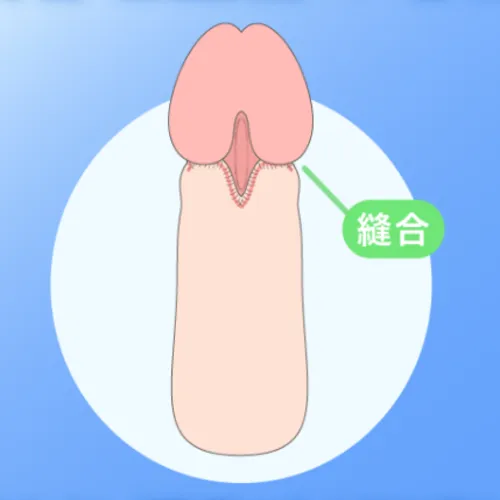

上野式包茎手術は、亀頭のすぐ下で縫合を行う「亀頭直下埋没法」を採用しています。縫合部分が亀頭の傘の下に隠れるため、傷跡が目立ちにくく、より自然な見た目を目指せるのが特徴です。

一方、環状切開による基本包茎手術は、陰茎の途中で包皮を切除して縫合する方法のため、包皮の色の違いが残りやすく、いわゆるツートンカラーになることがあります。

そのため、見た目の自然さや仕上がりにこだわりたい方には、亀頭直下埋没法を採用した上野式包茎手術が選ばれています。